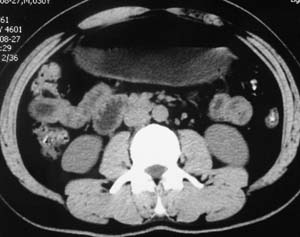

以下是引用子期在2010-3-19 20:47:00的发言:[br]血管畸形的ct增强应该有明显强化,本例并不相符合。本例双肾局部的略低密度影,累及肾盂,局部皮质明显变薄、内陷,增强扫描有轻度的强化,应考虑为炎性病变,患者为年轻男性,累及双肾的感染以结核较常见,可以没有明显的临床症状,尿中有时候也并不能查出什么;肾脓肿常有明显感染中毒症状,本例不符,另外一般的肾盂肾炎或肾小球肾炎通过小便就可确诊,其它还不能排除的是黄色肉芽肿性肾盂肾炎,然而单凭ct一般也很难鉴别。